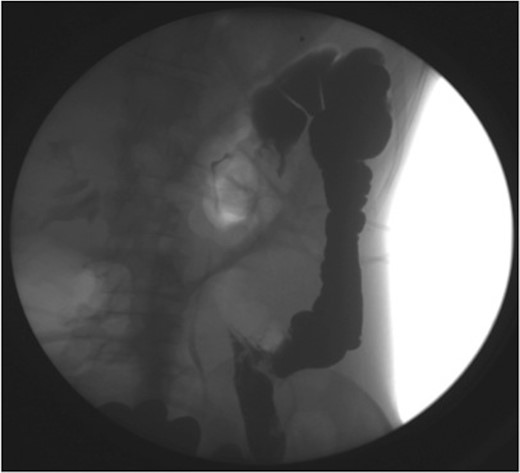

Haemoglobin was 14.9 g/dl and the white cell count (WCC) was 9 × 109/l. Other remarkable laboratory tests included a C-reactive protein (CRP) of 15 mg/l. Urinalysis was normal. The plain X-ray abdomen (AXR) (Fig. 1) revealed dilatation of a focal segment of large bowel with mildly dilated small bowel. Computed tomography (CT scan) of his abdomen reported that the gas-filled viscus is likely to represent the caecum (Fig. 2).

Plain AXR (Case 1) revealed dilatation of a focal segment of a large bowel with a mildly dilated small bowel.